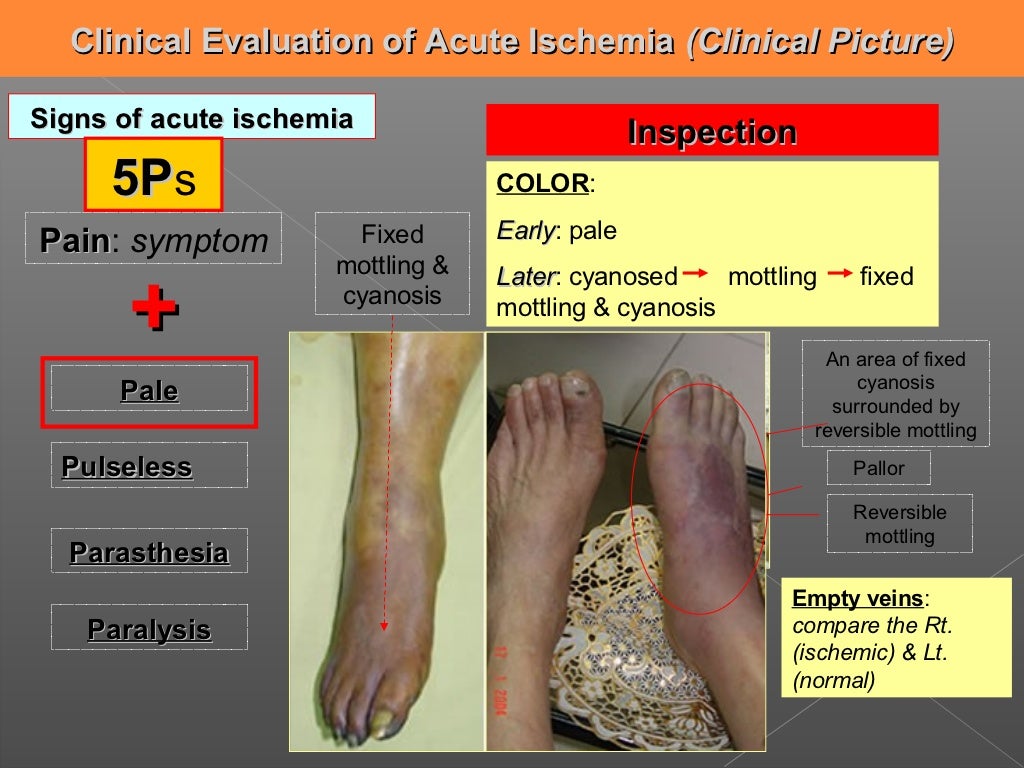

Ischemia is a vascular disease involving an interruption in the arterial blood supply to a tissue organ or extremity that if untreated can lead to tissue death It can be caused by embolism thrombosis of an atherosclerotic artery or trauma Venous problems like venous outflow obstruction and low flow states can cause acute arterial ischemia Ischemia is a condition in which the blood vessels become blocked and blood flow is stopped or reduced When blood flow is diminished to a body part that body part also does not receive adequate oxygen legs critical limb ischemia a form of peripheral artery disease and intestines acute mesenteric ischemia or bowel ischemia

Acute Limb Ischemia